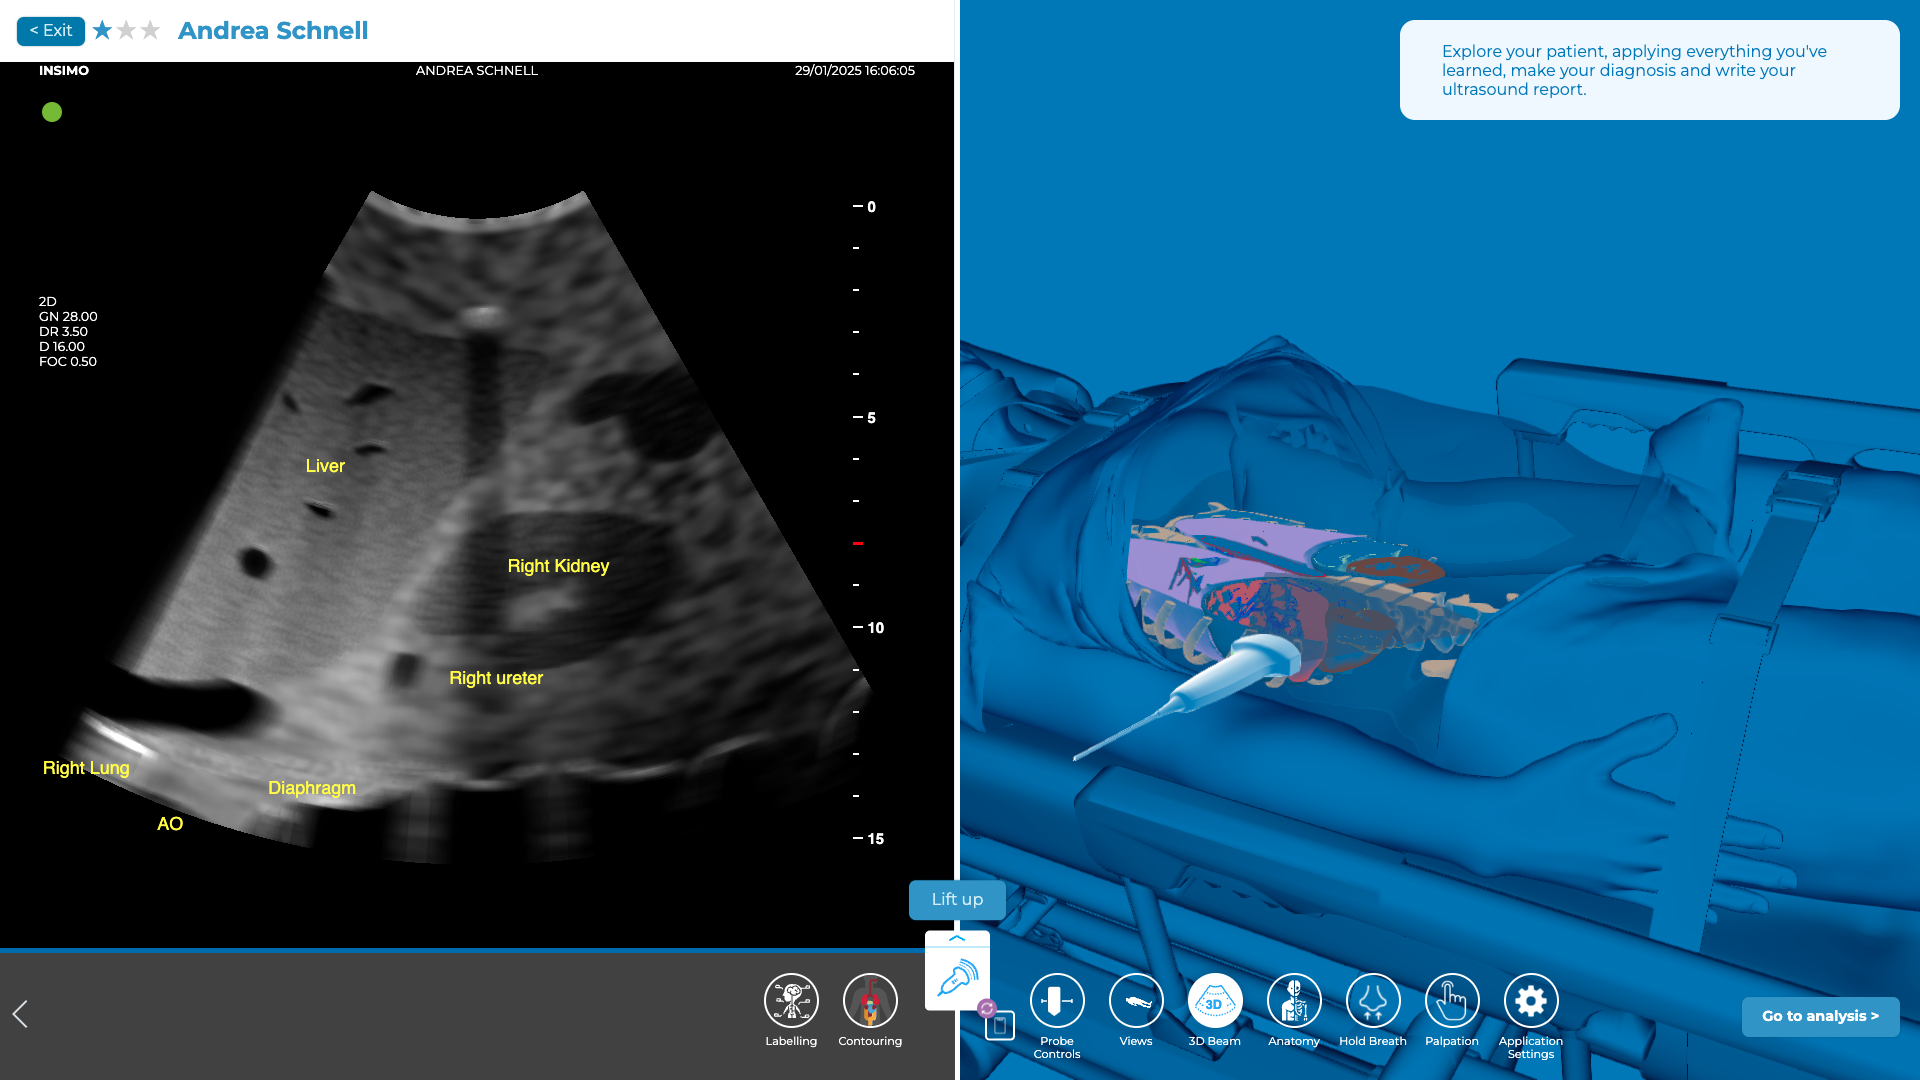

Evaluation du Quadrant Supérieur Droit (QSD)

En plaçant la sonde dans la région épigastrique, vous devez être capable d’évaluer le foie, le diaphragme et la cavité péritonéale. L’un des points clés à explorer est l’espace de Morison, qui se trouve entre le foie et le rein droit. La présence de liquide libre dans cet espace est un signe évocateur de traumatisme hépatique ou rénal, indiquant potentiellement une rupture ou un hématome [4].

Pour évaluer correctement cette zone, identifiez les 8ème et 11ème espaces intercostaux sur le patient et placez la sonde à leur niveau, en vous assurant qu’elle est positionnée juste au-dessus de la côte. Une approche plus précise consiste à utiliser la ligne axillaire antérieure comme guide pour aligner la sonde de manière appropriée sur le flanc droit. Si le patient est en mesure de le faire, demandez-lui de prendre une grande inspiration et de bloquer sa respiration. Cela permet de mieux visualiser la zone hépatorénale, car l’inspiration provoque une descente du diaphragme, ce qui permet d’obtenir des images plus nettes du foie et de la région autour du rein. Ensuite, balayez doucement l’espace de Morison (l’espace hépatorénal) pour rechercher la présence de liquide libre [2].

Exploration du QSD sur diSplay U/S